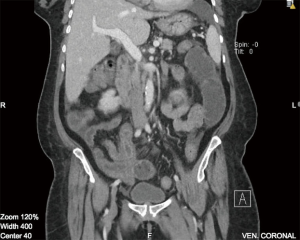

On imaging, plain film abdomen showed dilated small bowel loops and multiple air fluid levels on erect view. Chest X-ray showed no free air under the diaphragm. Computed tomography (CT) of the abdomen and pelvis with IV and oral contrast was done showing prominent dilatation of the jejunal small bowel segments, compatible with obstruction. On the jejunoileal junction and proximal ileal segments there was appearance of intussusception and thickened wall of the ileal segment (6 cm thickness) (Figure 1). Distal ileal and colonic segments were collapsed. There was perihepatic, perisplenic and intrapelvic free fluid. Furthermore, there was a small amount of free air focus in the subhepatic area (Figure 2) with bilateral small pleural effusions. No suspicious lymph nodes were detected.